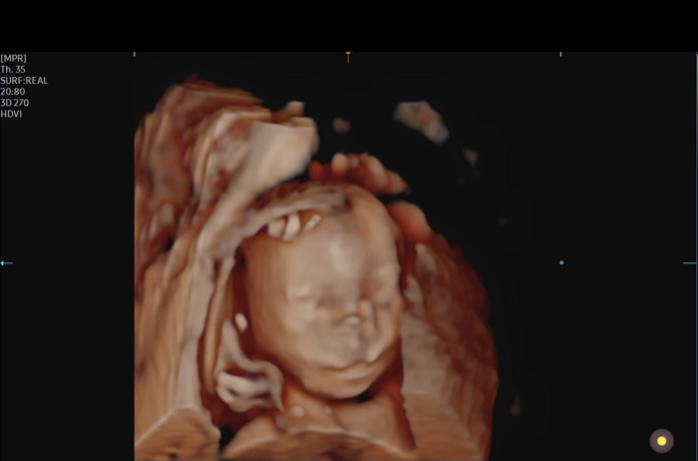

We had our halfway ultrasound and got to see our wiggly little guy! He was moving all over, but then refused to move when the tech needed him to so she could get a better angle. Such a stubborn little boy! Everything is measuring perfectly and all looks great, which is such a relief and we are so grateful! Little guy is moving a LOT now and I can feel him all the time, which makes it much more real that we’re actually having a baby!